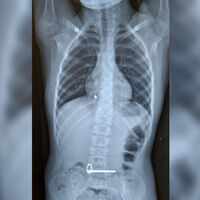

Школьник поступил в отделение экстренной помощи с подозрением на инородное тело в желудке. В ходе обследования было установлено, что мальчик проглотил два металлических ключа.